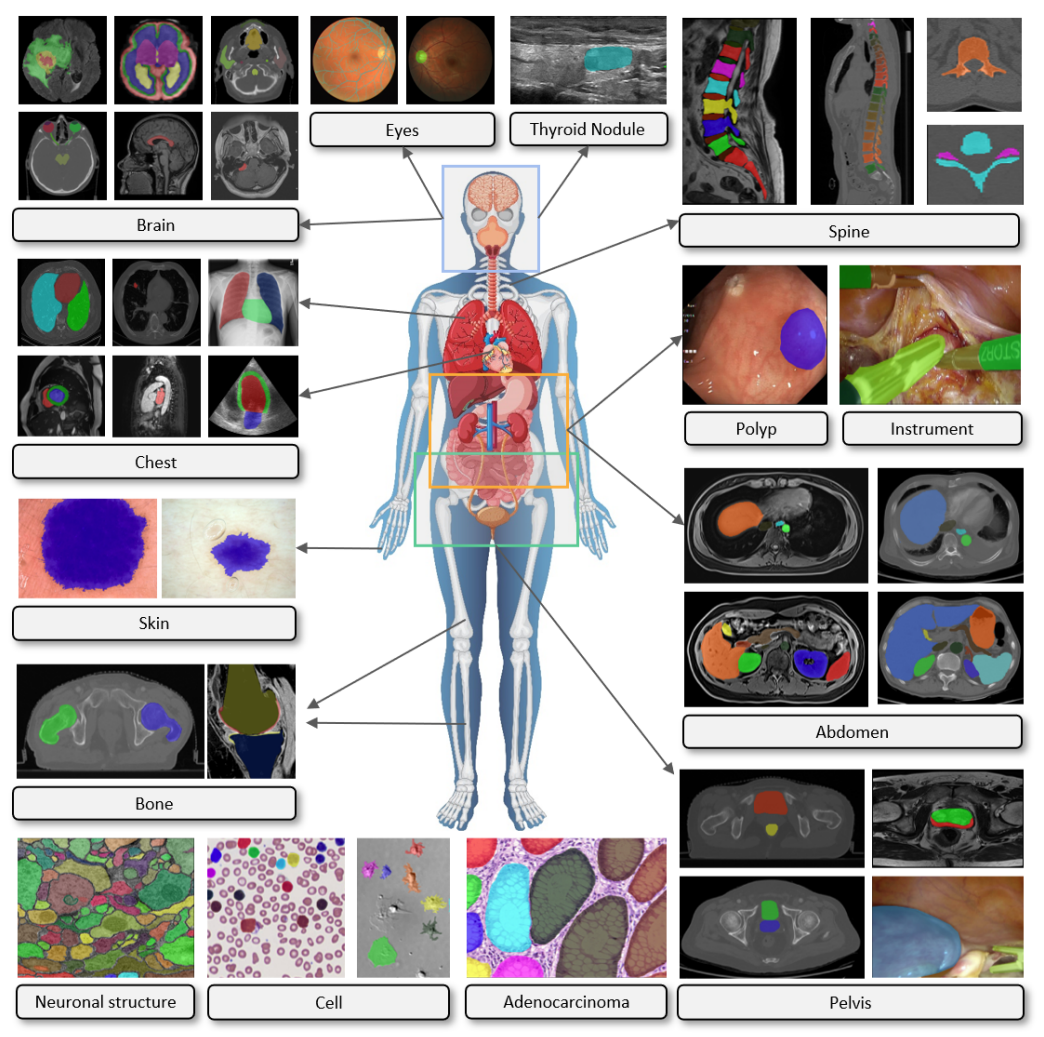

为了全面评估分析SAM在医学影像分割上的表现,团队收集并标准化了52个公共数据集,最终整理构建了一个包含16种影像模态和68种生物医学领域分割目标(表1)的大型医学影像分割数据集COSMOS 553K,数据集的展示见图1,统计信息见图2:

图1 COSMOS 553K涵盖了大多数医学影像模态和生物医学领域分割目标。例如,脑肿瘤、眼底血管、甲状腺结节、脊柱、肺、心脏、腹部器官或肿瘤、细胞、息肉和手术仪器等。人体图像来自Freepik,作者为brgfx(网址)